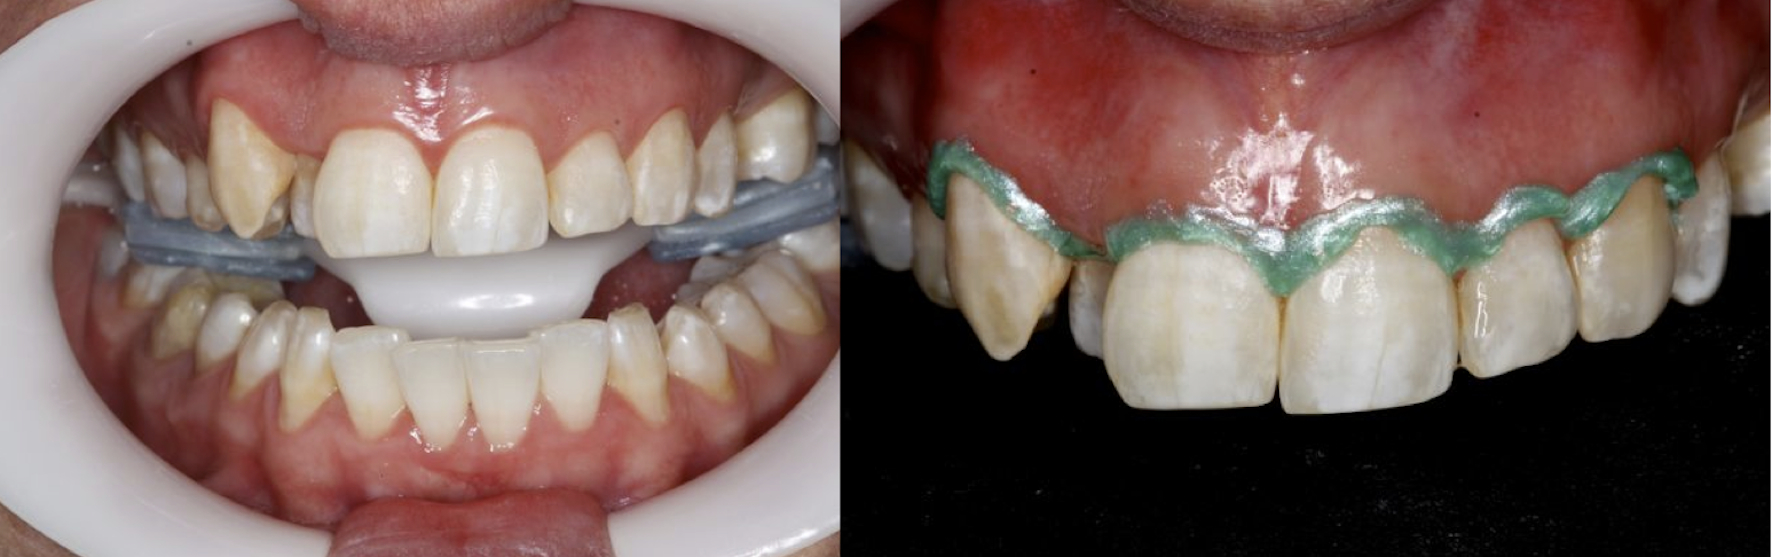

The generalized presence of stain, particularly on anterior teeth, provides an unaesthetic appearance with a negative impact on the patient. The aim of this paper is to report a case of severe chromatic alterations treated with enamel microabrasion associated with infiltration of low-viscosity resin. The intense brownish pigmentation and white spots of fluorosis lose their whitish appearance and look similar to sound enamel. This association of techniques, which might be an alternative to white-masking of intense pigmentation, showed optimal aesthetic results.